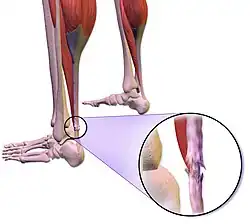

Other less localized injuries in the shoulder, knee, and Achilles tendon have also been noted to arise from playing the Nintendo Wii.[9][10][11] Some of the symptoms can be associated with the De Quervain syndrome (degeneration of tendons that control the movement of the thumb).

Achilles Wii-itis

Based on case reports, Achilles tendon injuries can happen with different degrees of severity while playing Wii. These injuries may include tear or complete rupture of Achilles tendon. The rupture of the tendon will require surgery, while minor tears can be addressed with non-surgical treatments like physical therapy and use of NSAIDs.[15] In 2009, a case report was published describing a 42-year-old woman who tore her left Achilles tendon after stretching her leg on her Wii Fit board.[9]